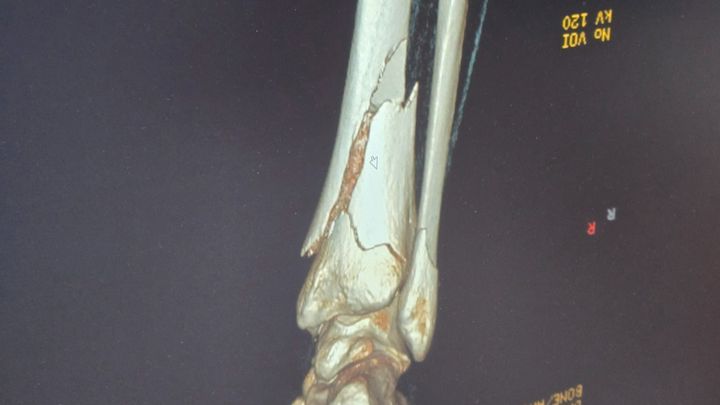

she suffered a serious accident that left her with both her tibia and fibula broken which haa cut her mission trip short. This injury means she’ll be unable to work for the next two to three months, with a likely return to work no sooner than February or more.